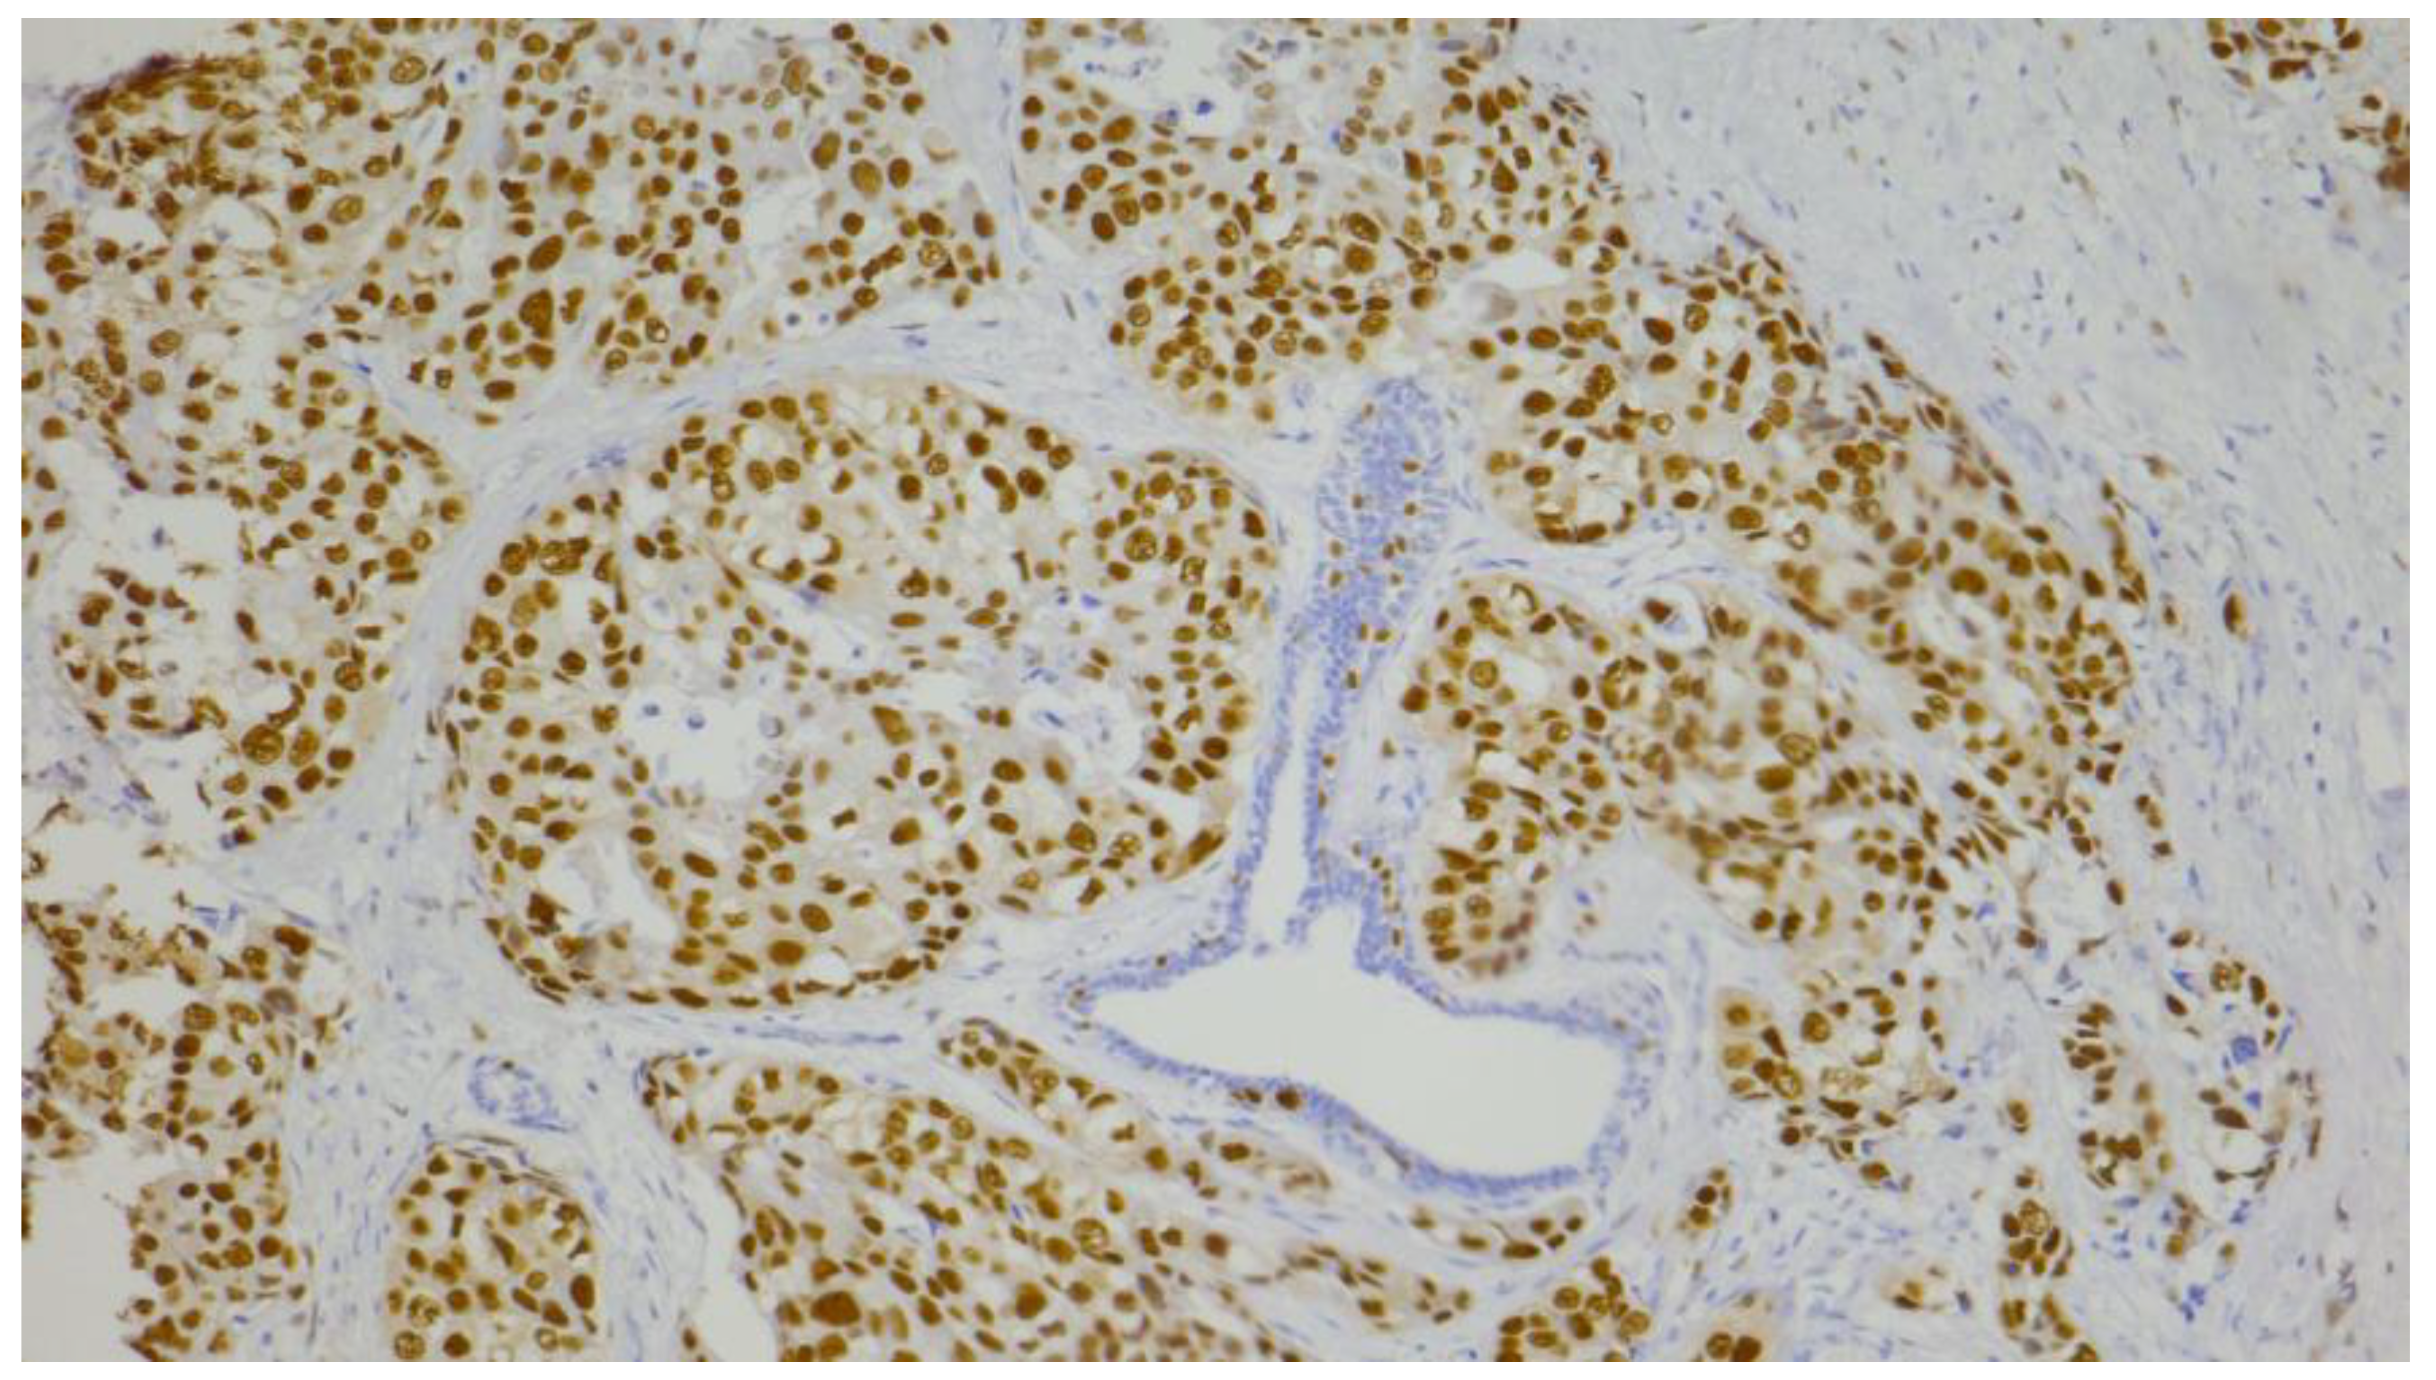

| Androgen receptor (AR) | n (%) |

| negative (≤10%) | 81 (65.3) |

| positive (>10%) | 43 (34.7) |